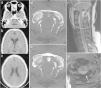

Hydrocephalus, an extremely rare complication of craniocervical junction injuries, is postulated to result from compression of the fourth ventricular cerebrospinal fluid (CSF) outlets by fractured and displaced bone fragments, a swollen upper spinal cord or adhesions formed after a traumatic subarachnoid haemorrhage. We present the case of a 21-year-old woman for whom an injury to the cervical spine complicated by a type I atlanto-occipital dislocation contributed to the development of non-communicating hydrocephalus. The hydrocephalus was probably a consequence of impaired CSF circulation at the fourth ventricular outlets (the foramina of Luschka and Magendie), caused by post-haemorrhagic adhesions formed after severe injury to the craniocervical junction.